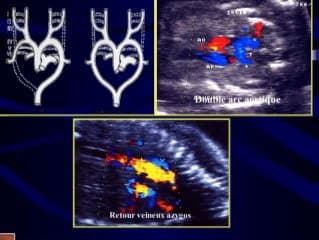

Incomparable leçon d'anatomie du coeur de Catherine LEPINARD qui nous interpelle à l'aide de coupes qui ne font pas partie des coupes du CTE, avec notamment la coupe des 3 vaisseaux, les crosses, les retours veineux notamment. Il est évident en regardant son topo qu'elles ne sont pas inutiles et qu'elles peuvent apporter des informations capitales, comme une crosse aortique droite, un retour azygos, une interruption de l'arche aortique par exemple, avec parfois la détection de 22 q 1.1 ou trisomie 21. Un regret, la qualité du son peu audible. Dommage...